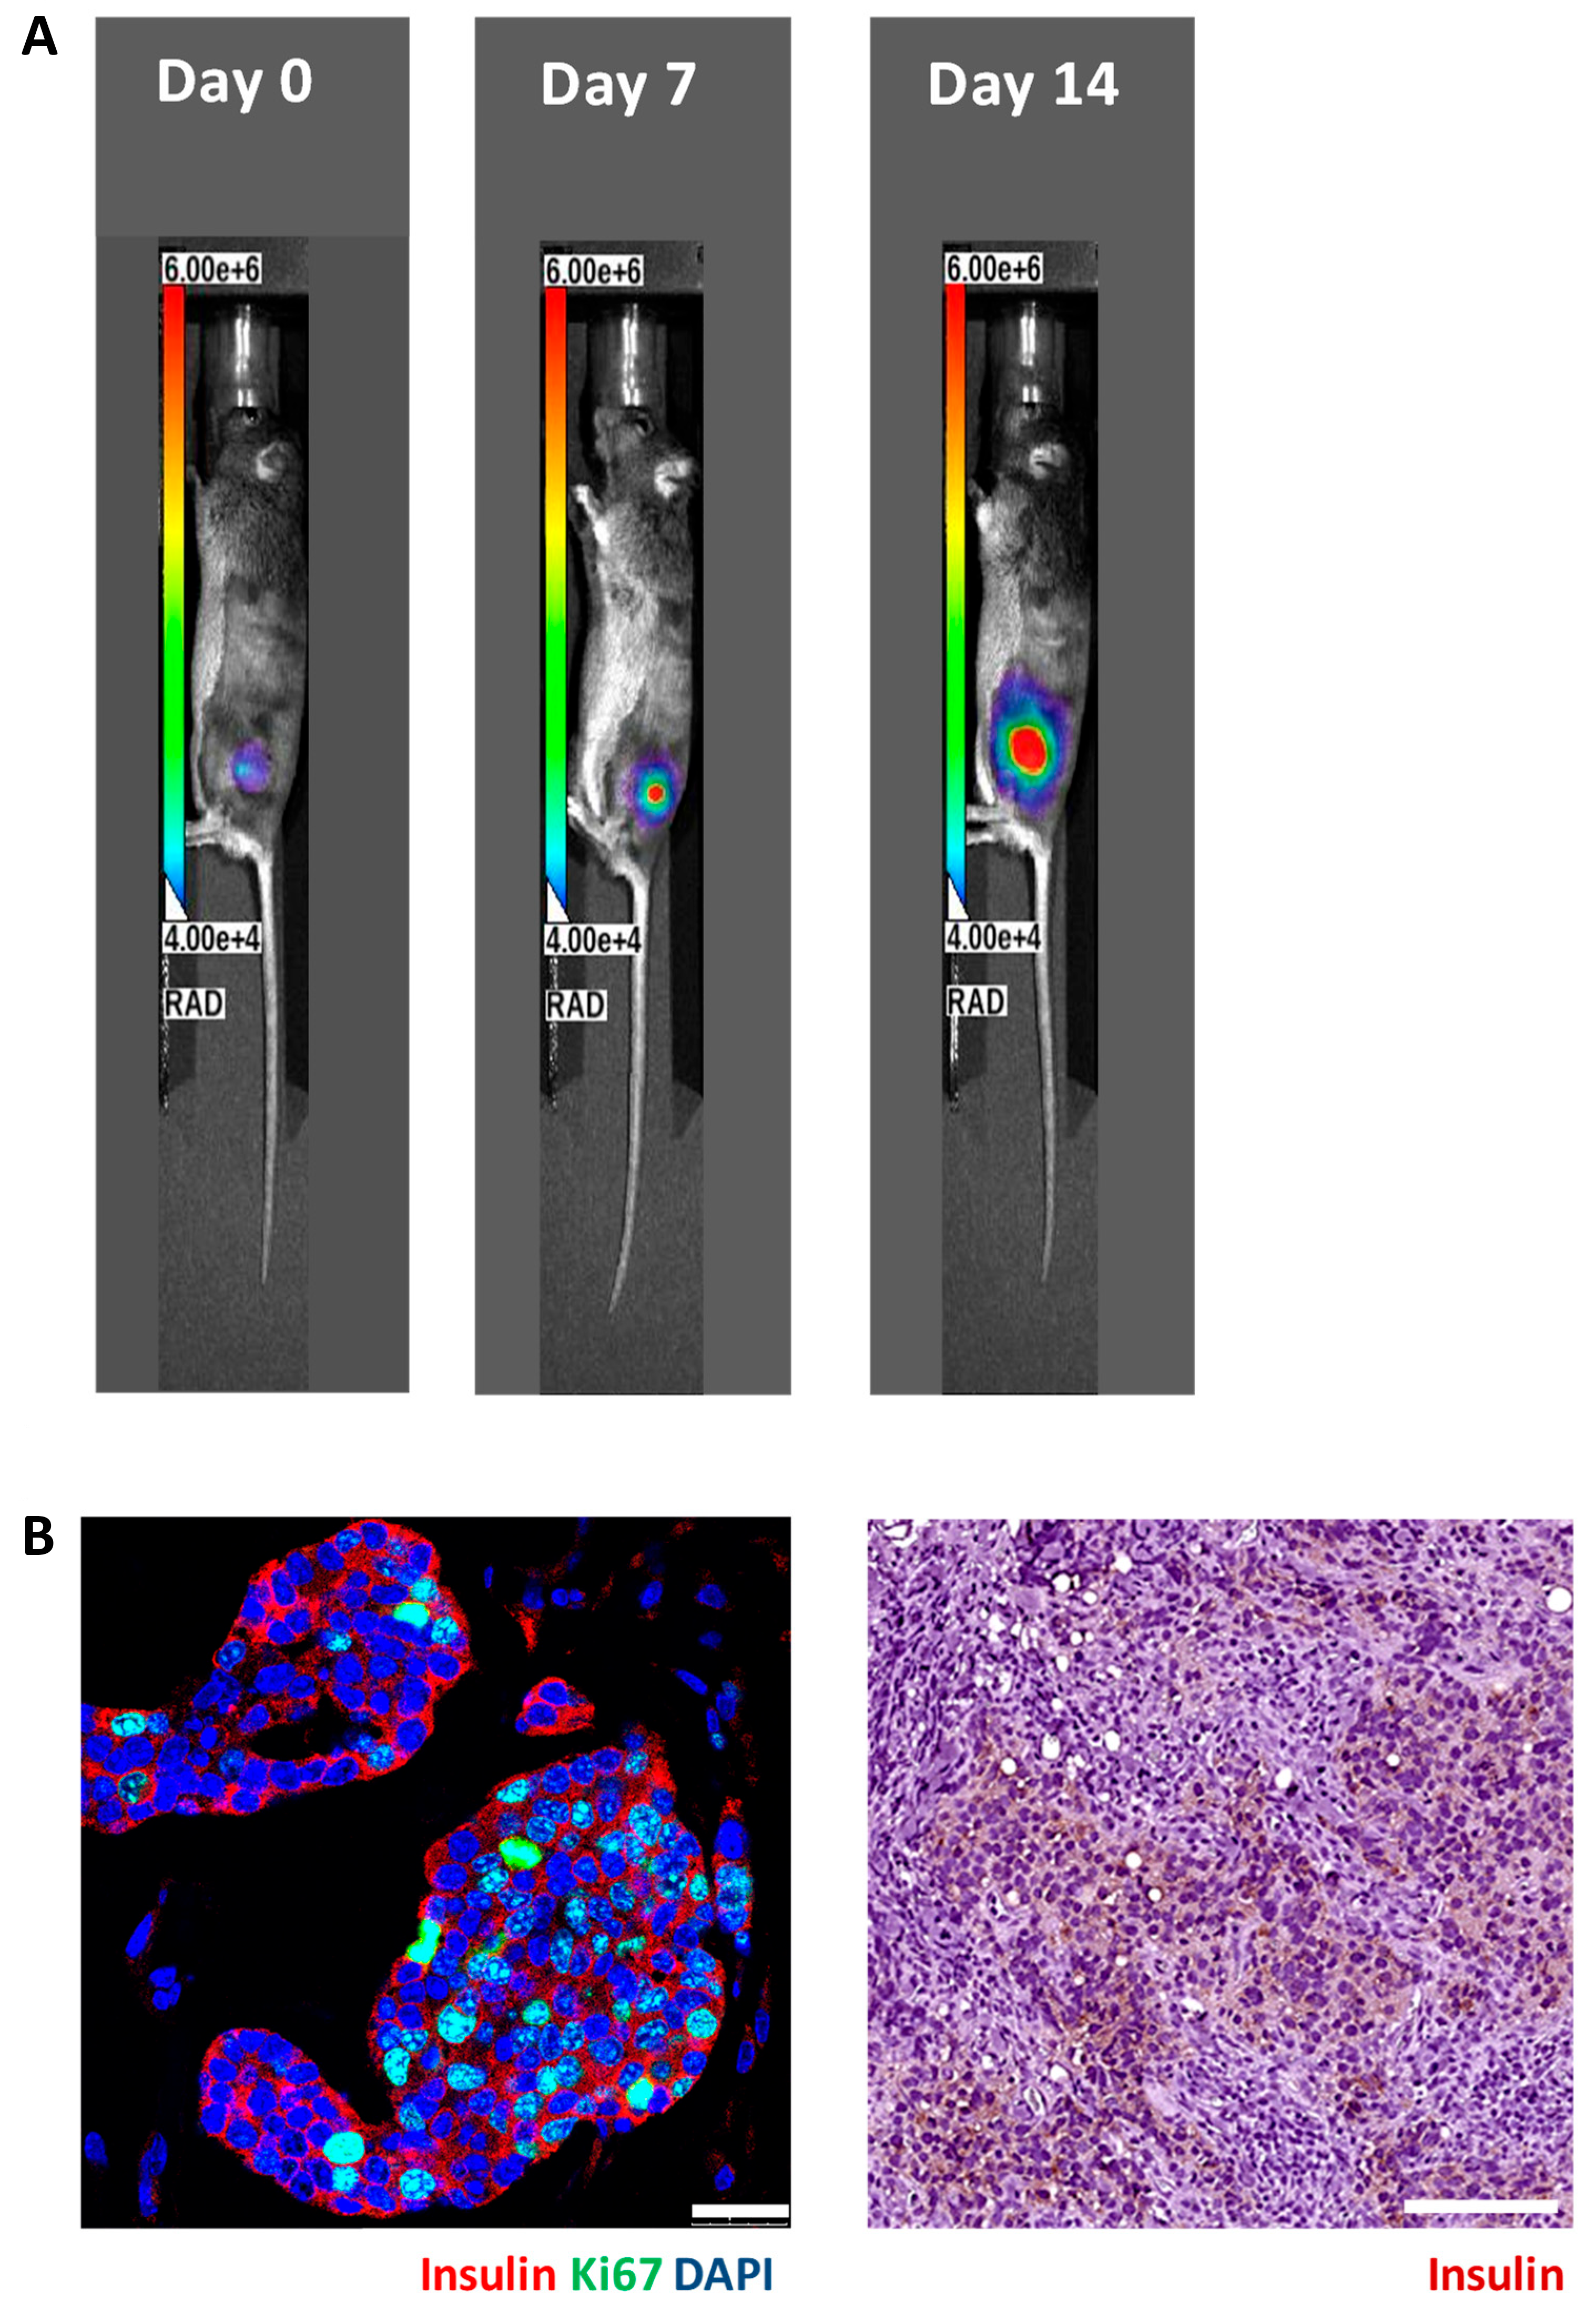

3.2. In Vivo Bioluminescence Imaging of Matrigel-Embedded MIN6 Cells Subcutaneously Transplanted in Nude and C3H Mice

3.3. Histology of Subcutaneous Matrigel-Embedded MIN6 Cell Grafts in Nude and C3H Mice